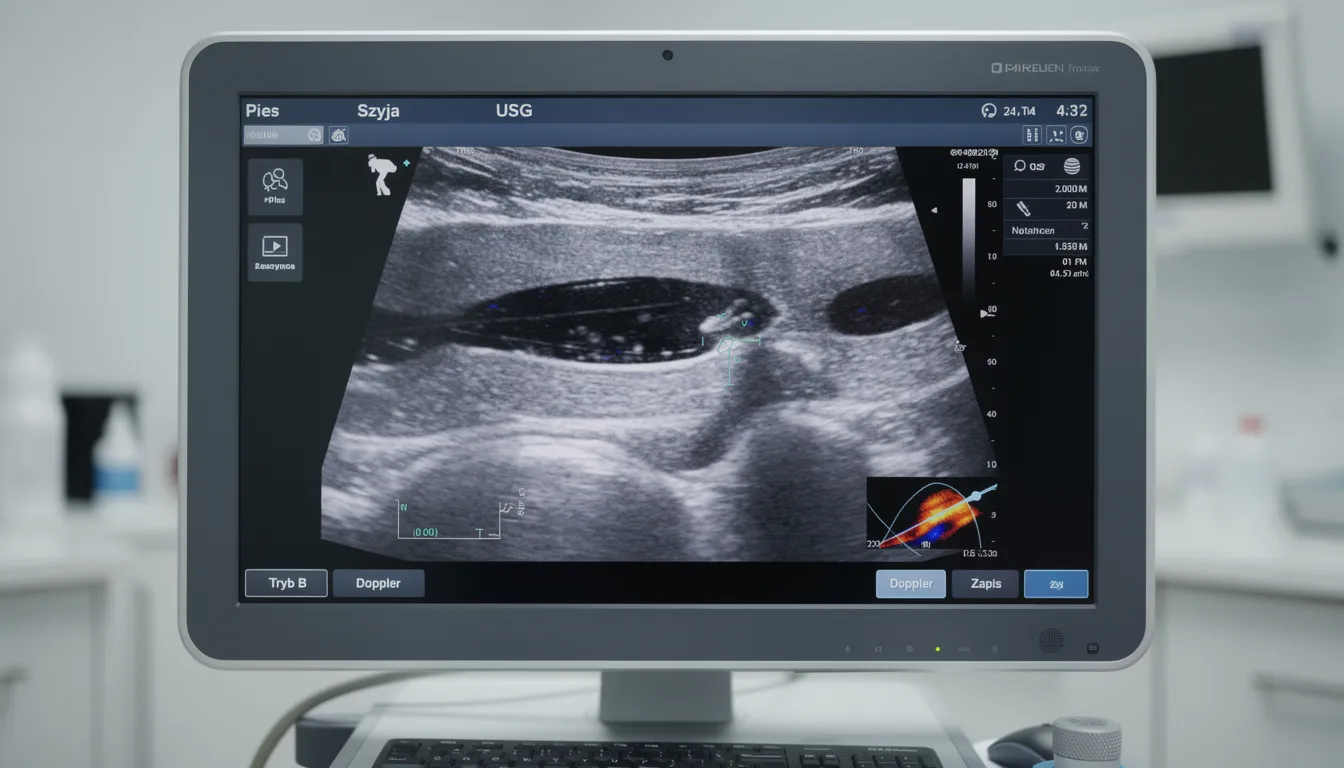

Diagnostyka obrazowa (USG, RTG, sialografia, TK)

Badanie ultrasonograficzne szyi i ślinianek jest badaniem pierwszego wyboru. Pozwala uwidocznić torbiele wypełnione płynem, pogrubione ściany gruczołu, obecność kamieni oraz ocenić otaczające tkanki.

| USG | Ocena torbieli, obrzęku, kamieni |

RTG i badania kontrastowe są przydatne do wykrywania złogów w przewodach, ich przebiegu oraz ewentualnych miejsc niedrożności. Tomografia komputerowa jest stosowana w trudniejszych przypadkach – przy podejrzeniu nowotworu, ciała obcego w szyi lub rozległych zmian naciekowych.